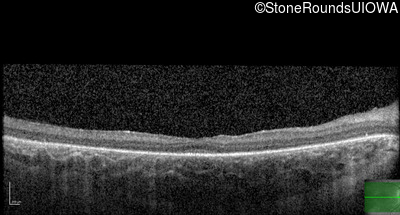

OD OS

Age at visit: 10 years

Age at visit: 11 years

Age at visit: 12 years

Age at visit: 13 years

Age at visit: 14 years

Age at visit: 16 years